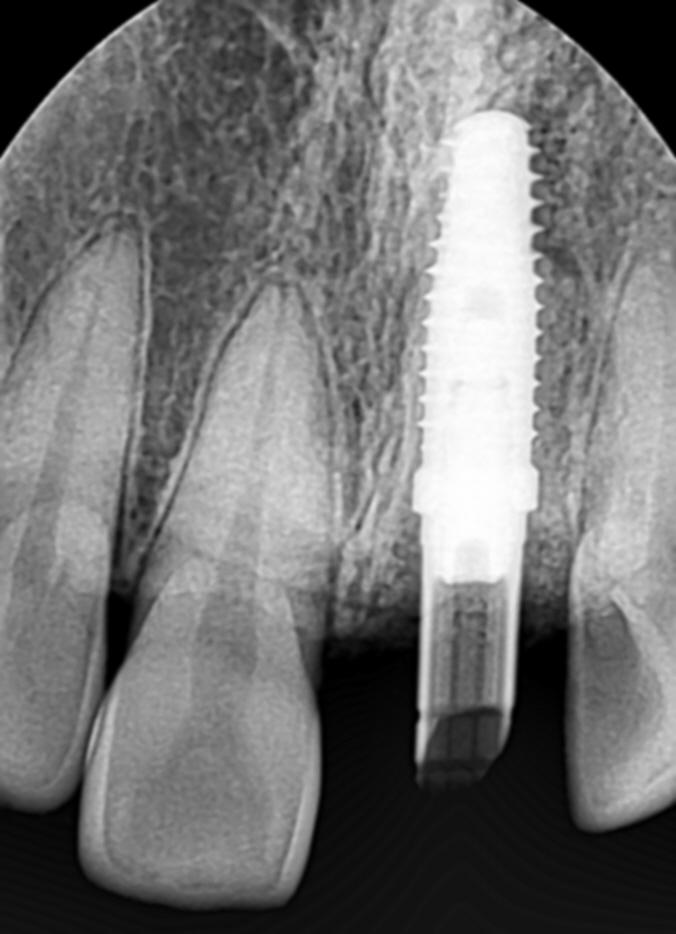

위의 장비들을 통해 얻은 3차원 정보는 즉시 컴퓨터로 전송돼 모의수술 단계를 거친다. 수술을 가장 안전하고 성공적으로 마칠 수 있는 방법을 찾아내는 것이다. 특히 이 모의수술 단계에선 최종보철물이 제작된다. 최종보철물이 바로 제작되는 덕분에 임플란트 식립 기간이 6개월에서 1일로 크게 줄었다. 예전에는 임시치아를 수술 당일에 끼우고 수개월 뒤 다시 내원해 최종보철물로 교체했다. 과거 진료 기간 연장의 주범이었던 아날로그 방식은 선치과병원에서 찾아볼 수 없다.

또 수술 완성도를 높이기 위해 수술 가이드를 제작했다. 수술 가이드는 구멍 뚫린 마우스피스 같은 모양을 하고 있다. 수술 시 이 구멍을 활용해 계획된 위치에 임플란트를 심게 되므로 잇몸절개 없이도 수술이 가능해졌다. 출혈이 적고 회복이 빠르다는 장점도 있다. 이러한 진료를 가능케 하기 위해 선치과병원은 첨단 장비들을 적극 도입했다. 현재 선치과병원은 ‘arum200’ 등 밀링머신 8대와 구강용 3D프린터(nextdent 5100, DIO PROBO 등) 7대를 보유하고 있다. 원래 3D 프린터는 주로 산업분야에서 사용됐지만, 2017년부터 치과에 도입되고 있다.